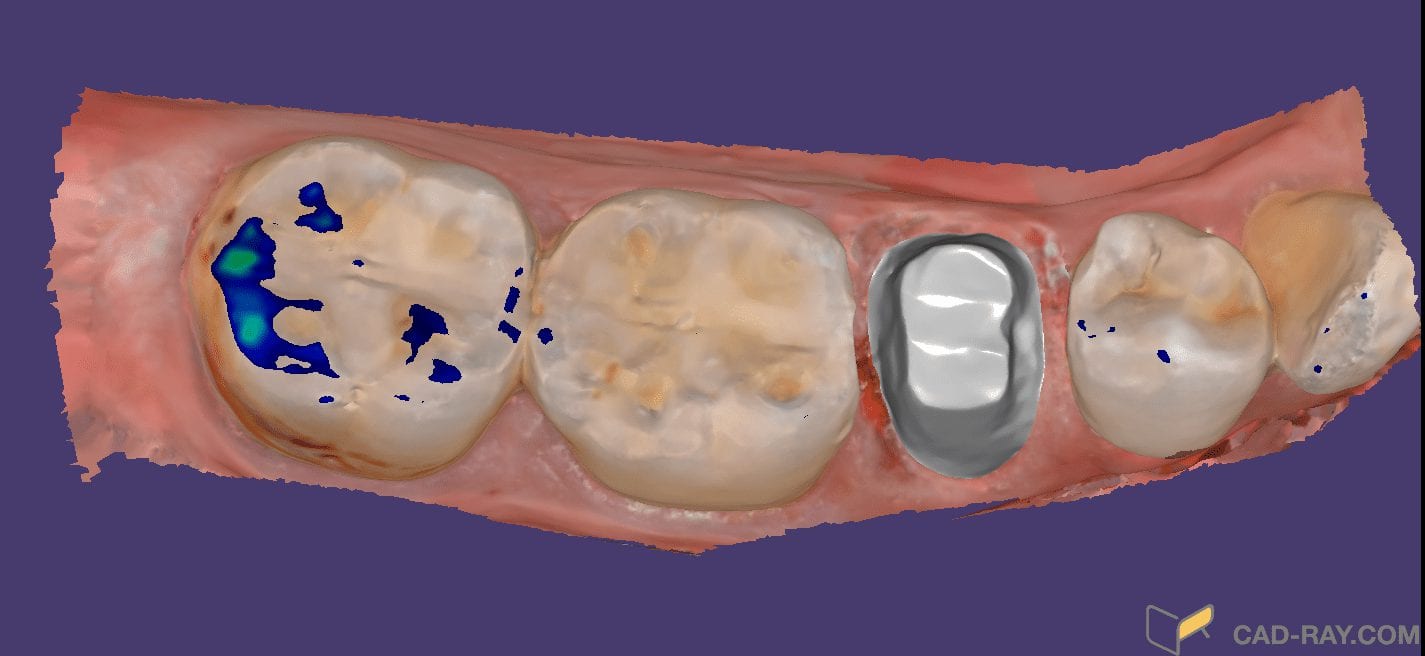

Milling A Lower Central Incisor in an eMax Size 12 Block on the VHF Z4 Milling Machine

March 29, 2019Time Stamps: This video is sped up at some points, but from the time the design was finished and it was sent to production, it tool less than 90 seconds […]